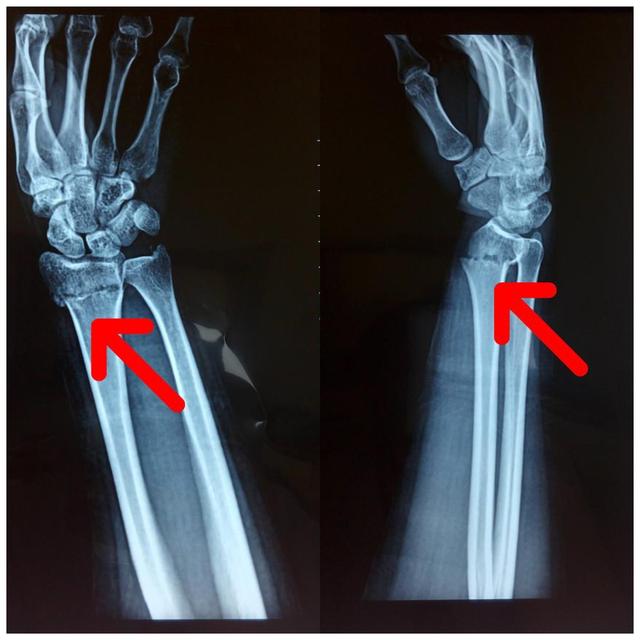

手法复位

桡骨远端骨折分型,桡骨远端骨折有哪些分型(桡骨远端骨折的AO分型)

复位后X片